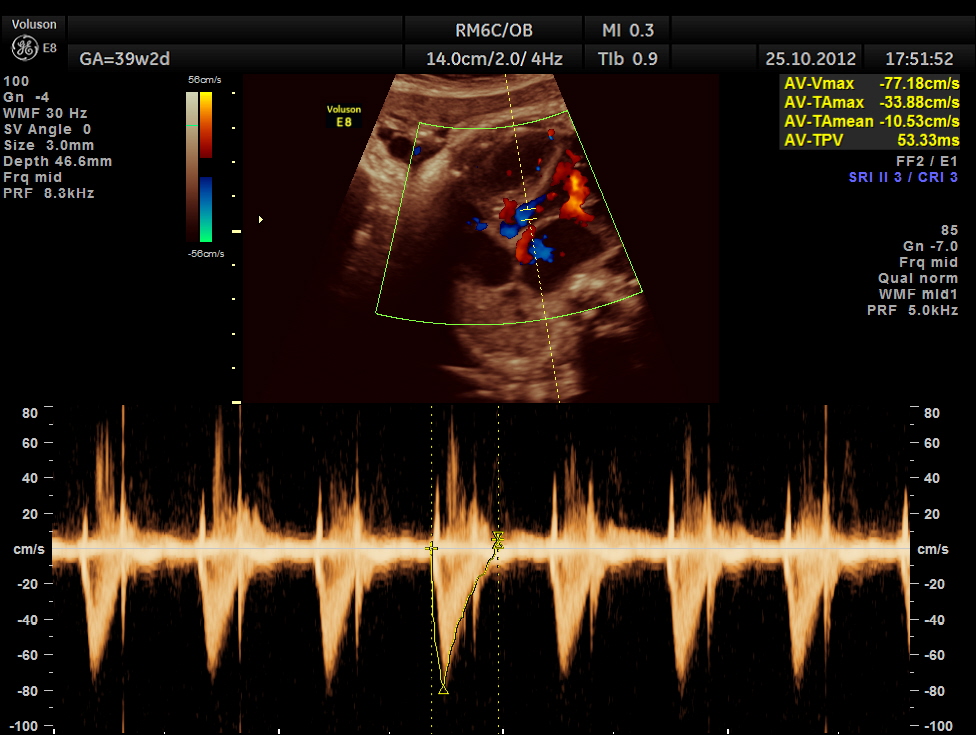

THIS FETUS HAD SEVERE FETAL ANEMIA WITH CARDIAC FAILURE LEADING TO CARDIOMEGALY WITH MITRAL, TRICUSPID AND PULMONARY REGURGITATION .NO OTHER OBVIOUS CARDIAC ANOMALY WAS MADE OUT . THE VENO ATRIAL , ATRIO VENTRICULAR AND VENTRICULO ARTERIAL CONCORDANCE APPEARED TO BE NORMAL; NO SEPTAL DEFECT WAS MADE OUT.